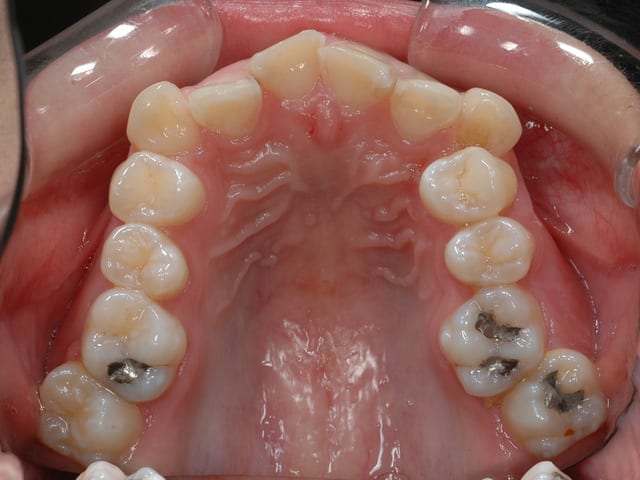

Si j'ai mis une vue vestibulaire et occlusal il y a une raison

Ronger des os n'expliquerait en rien ce type de lésion. La vue frontal et occlusal vous les détailles assez bien ainsi que les dents touchée.